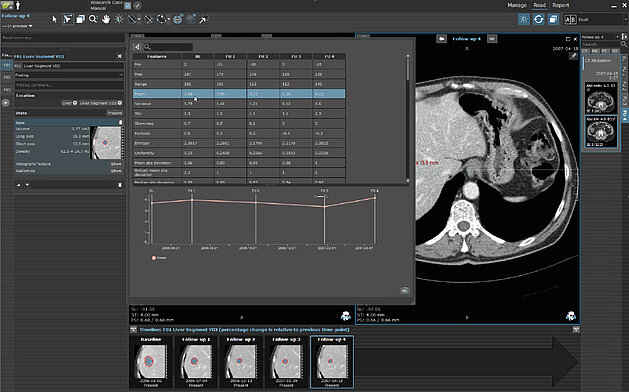

In a retrospective study [1], a team from Royal Marsden in London and Sutton explored changes of CT texture analysis metrics in unresectable liver…